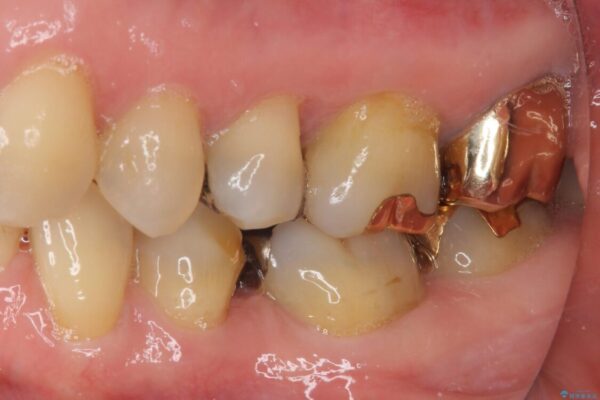

奥歯の銀歯が外れてしまったため、セラミック治療を希望された患者様です。

セラミックインレーによる修復治療を実施しました。

治療前

• 外れてしまった銀歯 セラミックインレーで自然な仕上がりに 治療前画像